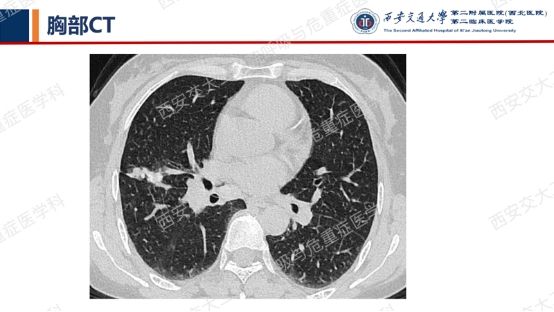

患者呼吸道症状并无太多特异性,还是从影像资料入手,右肺中叶外侧段高密度灶并纵隔及右肺门淋巴结肿大,同时存在双肺多发囊性病变,一元论?多元论?

囊性病变常要鉴别的疾病包括我们第一期的BHDLAM,还有LIP(淋巴细胞性间质性肺炎)、PLCH(肺朗格汉斯组织细胞增多症)、PLCDD(肺轻链沉积病)等。该患者囊性病变特点:沿支气管血管束周围分布,多个囊有血管贴边或穿行于囊肿壁。追问患者有口干不适,进一步行SS-A 52 101.65 AUSS-A 60 47.30AUANA 阳性(+),滴度1:10000 阳性(+),又经唾液流率、泪液流率、唇腺活检及风湿免疫科会诊,诊断干燥综合征。

需要强调的是,LIP影像表现较为复杂——弥漫性GGO+边界模糊之小叶中心性结节+胸膜下结节+支气管血管束增粗+多发囊样气腔各种征象可单独或同时存在。我们最近几期病例会聚焦在弥漫性囊性肺疾病,所以展示的病例影像基本以囊变为主。